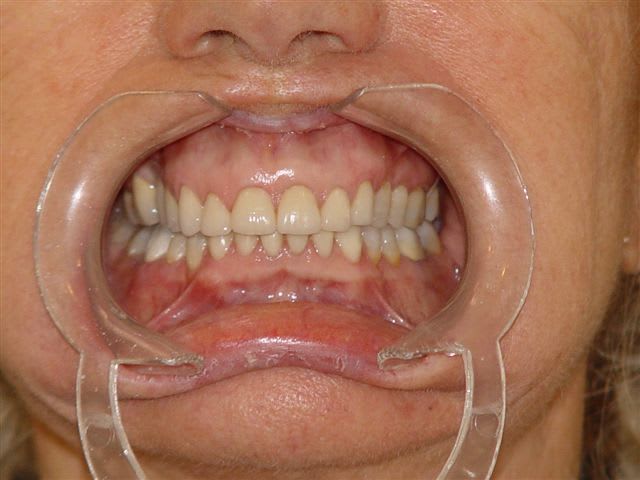

Bon je suis bien embêté avec mon grand père et je vous laisse juger par les photos.

Bon je fais une petite mesure rapide : 38 = 1,5mm de hauteur coronaire, et béance de près de 4mm au maximum

En plus, il a encore de super dents, non? et presque pas (voire peanuts) de pertes d'atache. En plus, il a un paro en béton.